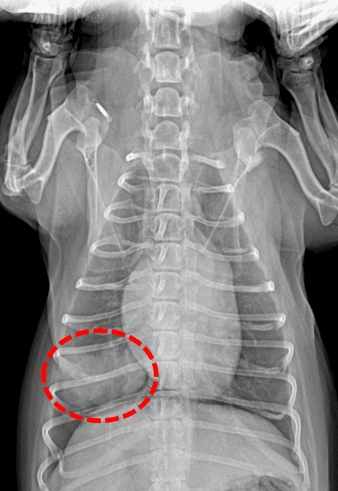

如何診斷狗腫瘤轉移肺部?

診斷需要多管齊下,獸醫通常會做以下檢查:

| X光檢查 | 查看肺部有無陰影或結節 | 最基礎的篩查,但小腫瘤可能漏掉 |

獸醫可能會建議從X光開始,如果發現異常,再進階到CT。活檢是黃金標準,但有些家長擔心風險,其實現在技術很安全。台灣大學獸醫專業學院有篇研究指出,早期診斷能顯著提升治療成功率。

我有個朋友帶狗狗做檢查時,獸醫用了X光發現肺部有多個小點,後來CT確認是轉移。他們慶幸沒拖延,否則後果更嚴重。